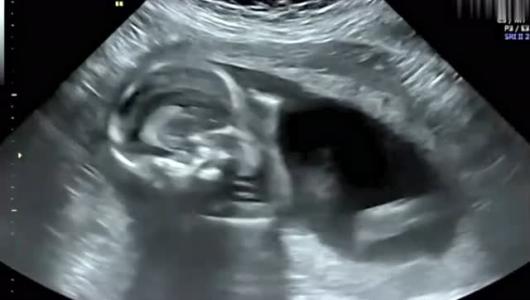

彩超不仅可以确定怀孕部位,还能直观地观察胚胎发育情况。宫外孕、剖宫产瘢痕妊娠、宫颈妊娠、葡萄胎等异常怀孕是不可以盲目保胎的。当然并不是所有的宫内怀孕都可以保胎,以下情况说明胚胎已经停止发育:胚胎头臀≥7mm仍探测不到胎心;胎囊平均直径>25mm没有出现胎芽;卵黄囊孕囊出现11天以上仍没有胎芽胎心;或两周以上仍看不到胎芽胎心、身体有缺陷,染色体异常,出生后可能会影响正常发育。这些情况就没必要保胎了,胎儿存活的可能性不大,出生后也不会幸福。